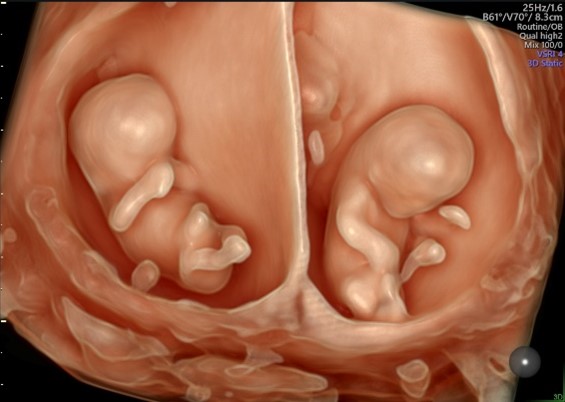

U svome je predavanju dr. Stanojević prikazao kako se plod kreće u maternici prije rođenja i do kojih se zaključaka došlo promatrajući ga zahvaljujući modernoj tehnologiji, odnosno četverodimenzionalnom ultrazvuku. Čini se da se uspjelo zaviriti u tajanstveni svijet prije rođenja koji je čudesan, istovremeno i vrlo bogat i dinamičan, ali i interaktivan, što potvrđuju mnoge majke, ali i znanstvena istraživanja.

Proučavajući ponašanje djeteta pomoću četverodimenzionalnog ultrazvuka, nagađalo se o njegovoj svijesti i kognitivnoj funkciji, pokušavajući se upoznati s njegovim emocionalnim životom i njegovom spremnošću da se nakon rođenja odvoji od majke i okoliša u kojem se poput astronauta lakše kreće i živi te započne samostalan život kao dijete – novi pojedinac. O svemu tome moglo se čuti tijekom predavanja uz prikaz videoisječaka iznimno zanimljivog i oku brojne publike uglavnom nepoznatog ponašanja ploda u utrobi majke. Na kraju predavanja koje je proteklo u vrlo ugodnoj atmosferi dr Stanojević je odgovarao na pitanja zainteresirane publike i svima poželio sretan Božić i dobro zdravlje u novom ljetu.

U ovome predavanju predavač će pokušati prikazati kako se plod kreće u maternici prije rođenja i do kojih se zaključaka došlo promatrajući ga četverodimenzionalnim ultrazvukom. Čini se da se uspjelo zaviriti u tajanstveni svijet prije rođenja koji je misteriozan, ali istovremeno i vrlo bogat i dinamičan, ali i interaktivan, što potvrđuju mnoge majke, ali i znanstvena istraživanja.

Proučavajući ponašanje ploda pomoću četverodimenzionalnog ultrazvuka, nagađalo se o njegovoj svijesti i kognitivnoj funkciji, pokušavajući se upoznati s njegovim emocionalnim životom i njegovom spremnošću da se nakon rođenja odvoji od majke i okoliša u kojem se poput astronauta lakše kreće i živi te započne samostalan život kao dijete – novi pojedinac.

O svemu tome moći ćete čuti tijekom predavanja uz prikaz videoisječaka ponašanja ploda proizvedenih četverodimenzionalnim ultrazvukom.